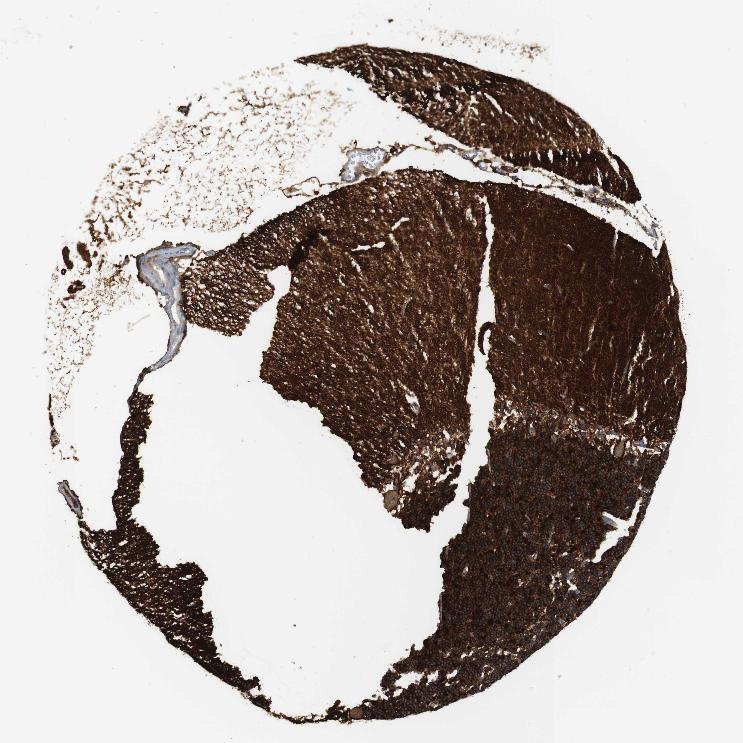

CEREBELLUM - Antibody stainingi

Antibody staining in the annotated cell types in the current human tissue is reported as not detected, low, medium, or high, based on conventional immunohistochemistry profiling in selected tissues. This score is based on the combination of the staining intensity and fraction of stained cells.

Each image is clickable and will lead to virtual microscopy that enables deeper exploration of all samples and also displays staining intensity scores, fraction scores and subcellular localization as well as patient and tissue information for each sample.

Antibody HPA054437Antibody HPA058511Antibody CAB002776Antibody CAB015122

Cells in granular layer High-HighHigh

Cells in molecular layer Not detected-MediumHigh

Molecular layer - neuropil -Medium--

Synaptic glomeruli - core -High--